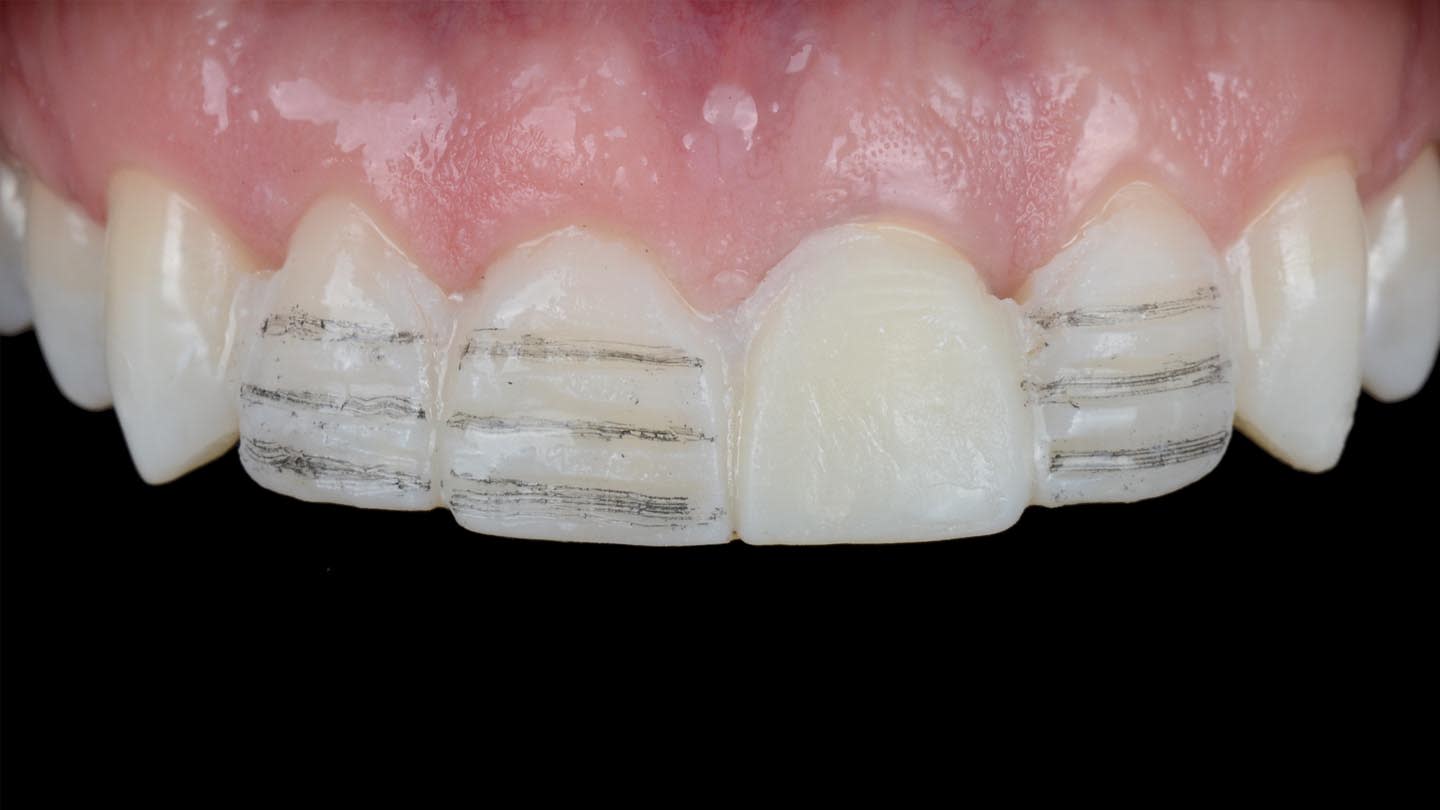

Consistent measurements act as a strict quality control mechanism, ensuring precision and accuracy throughout the design and treatment process.9-11 When planning esthetic restorative cases on patients with high expectations, the use of a wax-up and mock-up is essential for effective communication.12 The mock-up technique allows for a 3-dimensional (3D) visualization of the anticipated result over time, including tooth proportion, morphology, phonetics, amount of tooth reduction, and functional and esthetic analysis, making it often preferable to 2-dimensional (2D) and 3D chairside image modification software.13,14 For the present case, after the smile design was confirmed, an extra analog wax-up was performed to provide more details and to facilitate fabrication of an intraoral direct mock-up using a silicone index and a bis-acryl material, which also served as a guide for tooth preparation (Figure 3). After analyzing the mock-up and making minor esthetic adjustments, a digital impression was captured to emulate the future design of the final restorations.

Veneer preparations on teeth Nos. 7, 8, and 10 were performed according to the APT (“aesthetic pre-evaluative temporary”) protocol,13 guided by the definitive mock-up that visualizes the final shape of the teeth to be restored. The previous silicone index was also used to check the preparation depths. Upon approval from both the clinician and patient, the intraoral mock-up serves as a precise guide for shaping the tooth structure according to the planned final contours. This ensures that only minimal preparation of the tooth structure is performed, or in some cases, no preparation may be required in certain areas. Depth cutter burs were used to achieve the treatment goals while preserving as much natural tooth structure as possible.